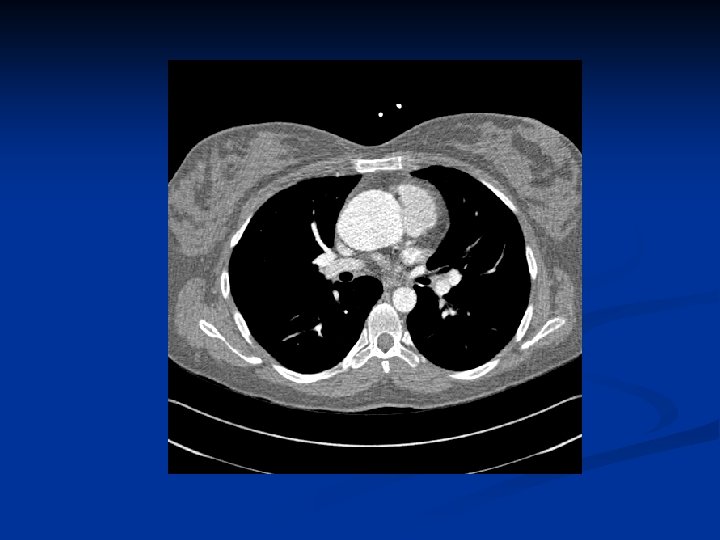

Cardiovascular n Major criteria: n Aortic-root dilatation: ( 70 -80%) n Aortic dissections involving the ascending aorta n Minor criteria: n Mitral valve prolapse (55 -69%) n Dilatation of proximal main pulmonary artery without pulmonic stenosis or other cause n Calcification of mitral annulus (patients <40 y) n Dilatation of abdominal or descending thoracic aorta (patients <50 y) n For the CV system to be involved, need 1 minor criterion

Echocardiography Diagnosis and management of aortic-root dilatation The upper limit of the normal aortic root size is 1. 9 cm/m 2 of body surface area n Assesses mitral-valve prolapse, LV size / function, LA size, and tricuspid valve function n TEE assesses the distal ascending and descending aorta and prosthetic valves n Doppler echocardiography - detecting and grading aortic and mitral regurgitation n

CT and MRI for assessing chronic dissection of the aorta - any patient who has an aortic-root dimension >150% of the mean for their body surface area or - ratio of actual to predicted aortic-root dimension >1. 5 n CT or MRI of the lumbosacral spine to evaluate for dural ectasia n

Treatment n Cardiovascular surgery CV surgery can substantially prolong survival Prophylactic / emergency CV surgery is needed for: - aortic and mitral regurgitation - aortic aneurysm - aortic dissection n In cases of acute proximal aortic dissection, emergency surgical replacement of the aortic root is performed n

Treatment The ascending aorta is usually replaced when the diameter exceeds 55 -60 mm n Composite valve-graft replacement is performed - prosthetic valve sewn into a tube graft with reimplantation of the coronary ostia (modified Bentall procedure) n Low rates of morbidity and mortality n